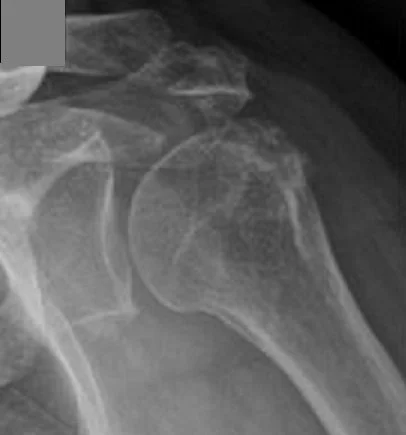

erosion of the humerus can occur with septic arthritis.